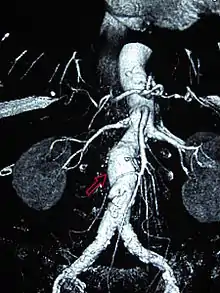

A 6.5 cm AAA with a 3 cm lumen

An aortic aneurysm can occur as a result of trauma, infection, or, most commonly, from an intrinsic abnormality in the elastin and collagen components of the aortic wall. While definite genetic abnormalities were identified in true genetic syndromes (Marfan, Elher-Danlos and others) associated with aortic aneurysms, both thoracic and abdominal aortic aneurysms demonstrate a strong genetic component in their aetiology.[11]